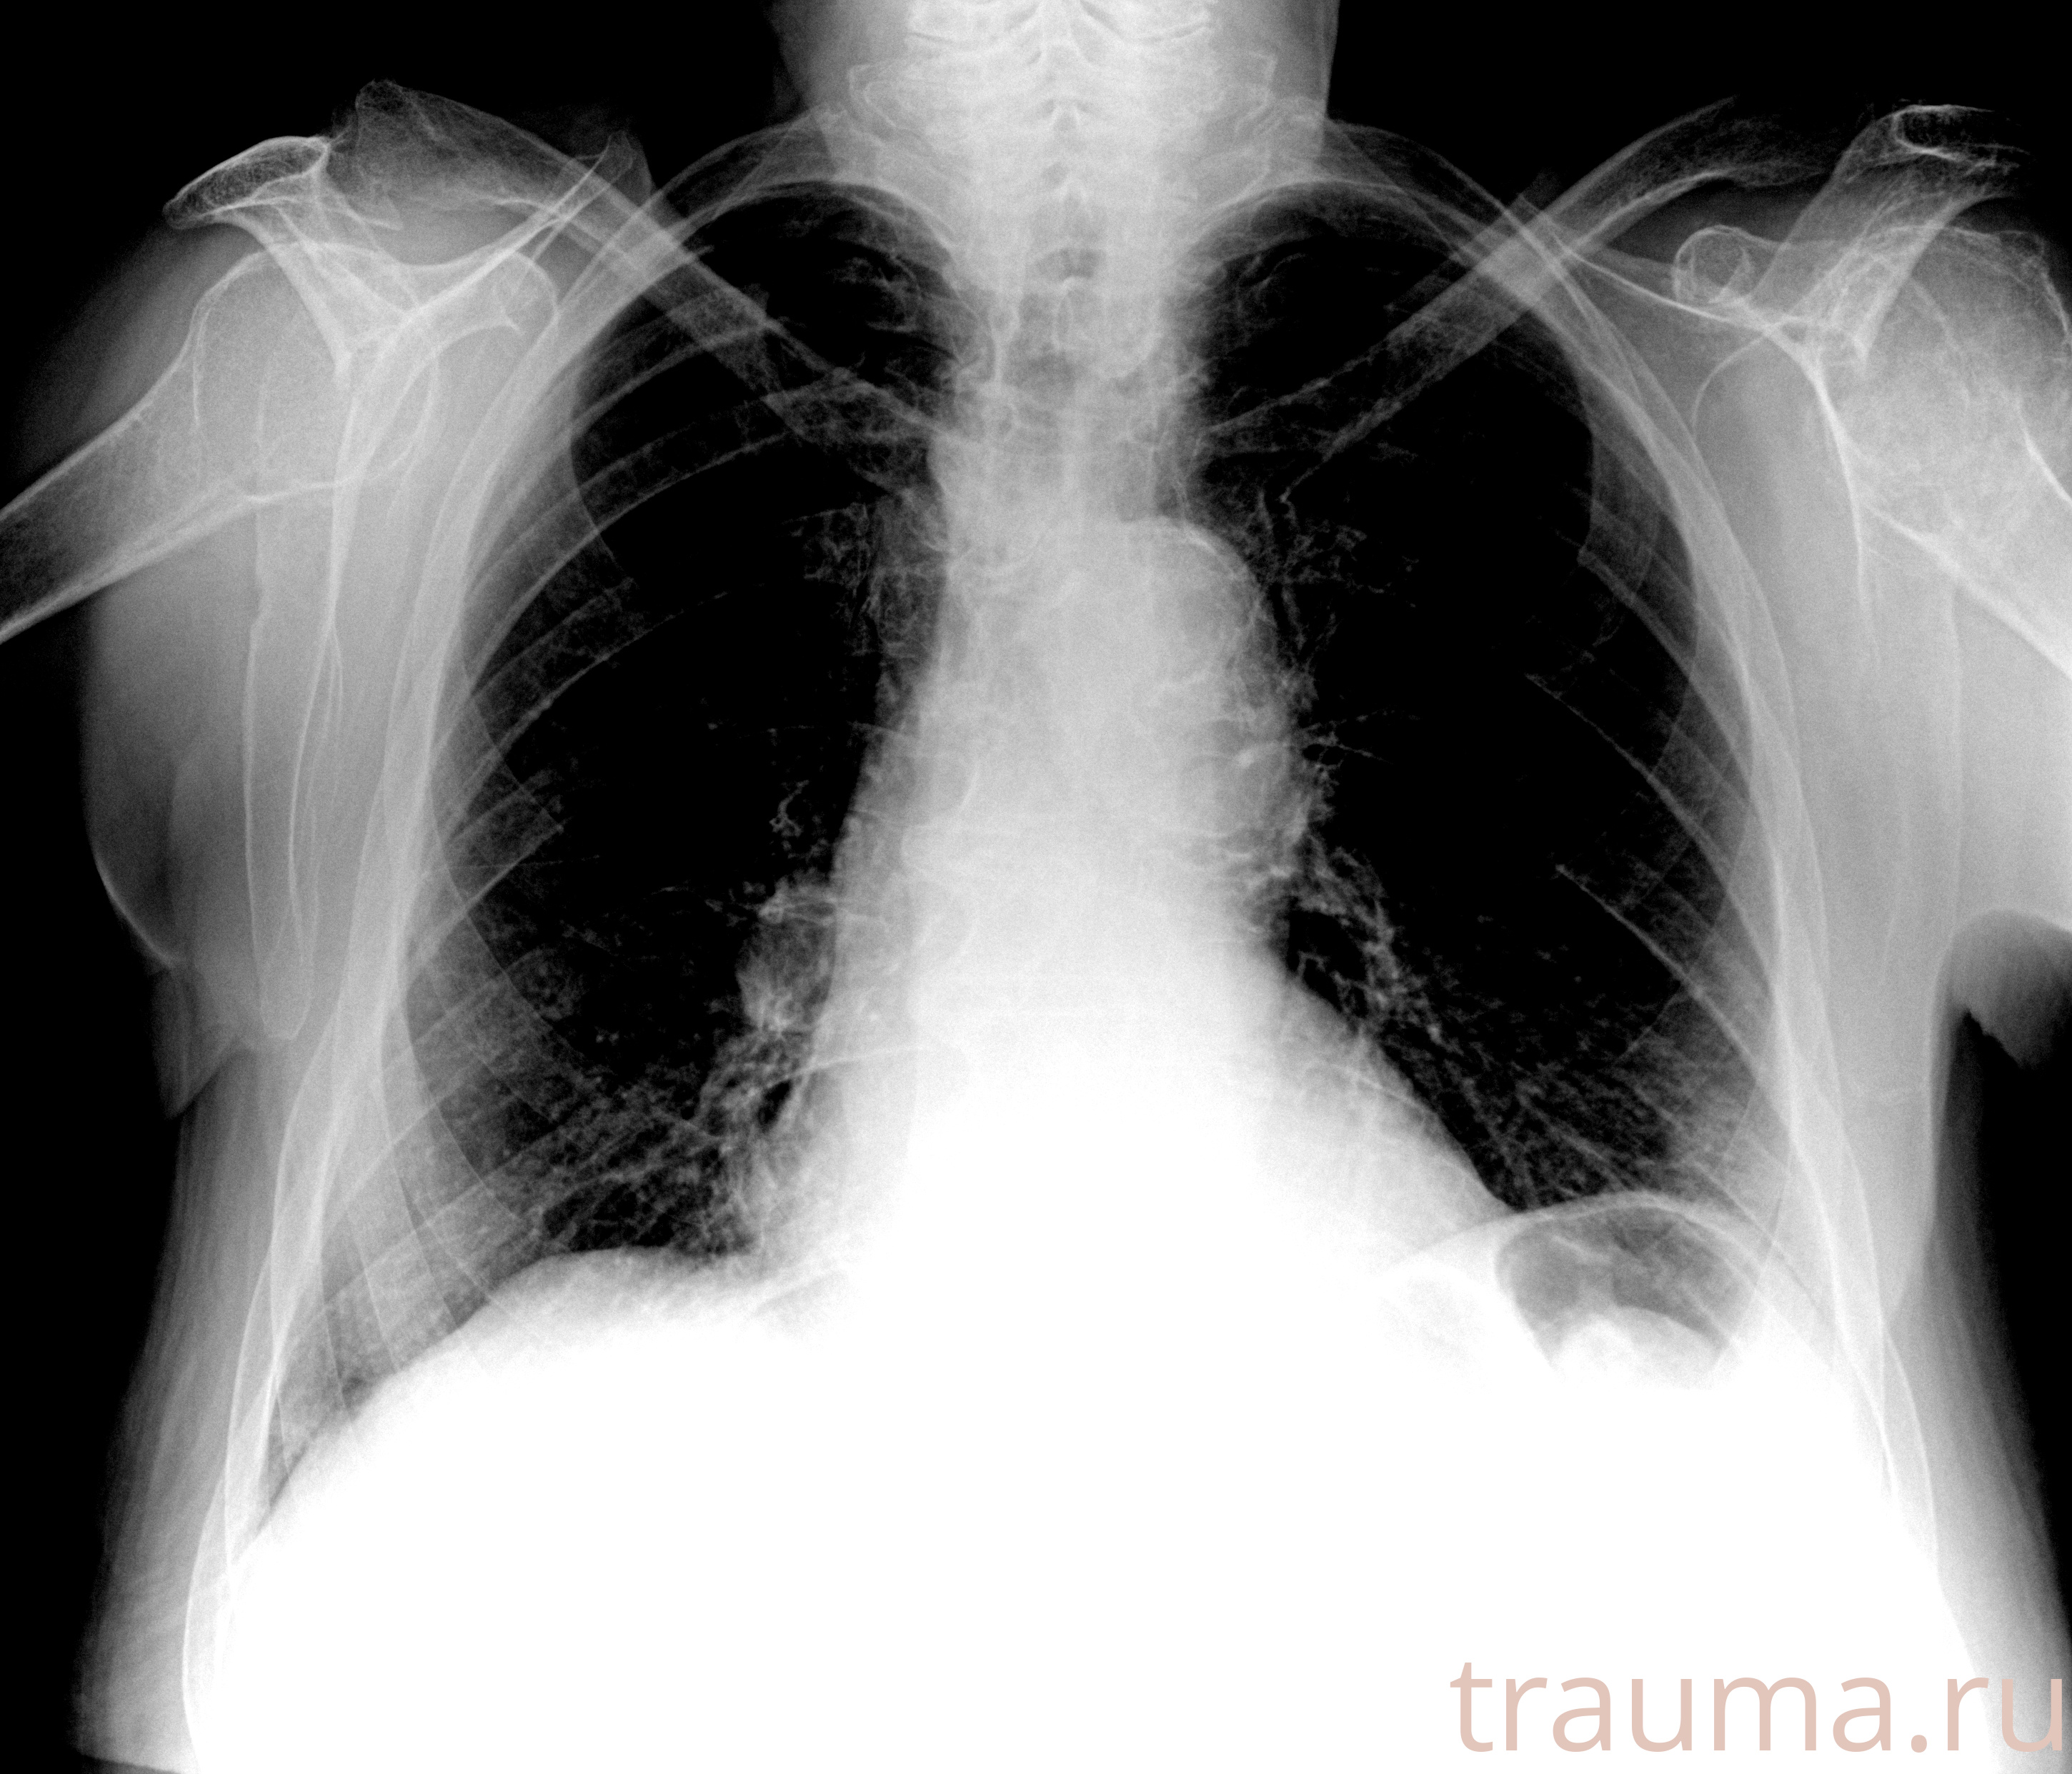

Рентген на дому: по вашему адресу приезжает врач-рентгенолог, травматолог-ортопед с мобильным рентгеновским аппаратом, проводит диагностику травмы или заболевания, делает необходимые рентгенограммы, дает рекомендации по дальнейшему лечению. Получить качественные снимки в домашних условиях возможно благодаря уникальной методике, разработанной МосРентген Центром для института  Склифосовского